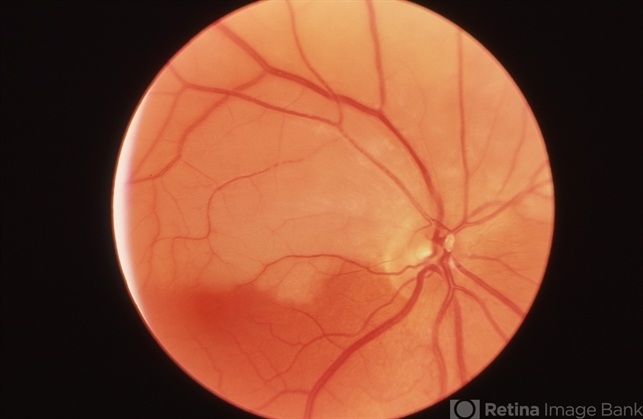

- CRAO

- central retinal artery occlusion (CRAO), embolus

- Right eye of a white female showing an embolic superior hemi-central retinal artery occlusion with the embolus visible at the main artery bifurcation on the optic disc.